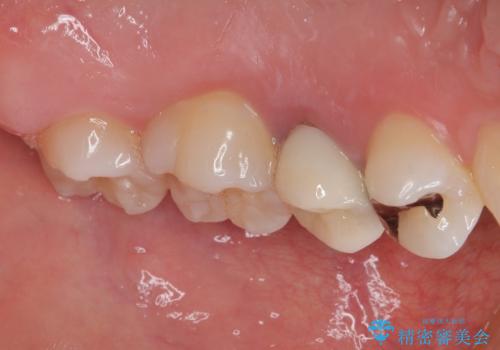

- 笑った時に目立つ銀歯を治したいとのことで来院された患者様です。検査の結果、オールセラミッククラウンによる補綴治療を行っていくことにしました。

拡大鏡視野下で銀歯を外し、オールセラミッククラウンに適した形に整えました。

歯と歯茎の間に圧排糸と言われる糸を入れてシリコーン印象材にて型どりをしました。

また、根管治療、土台のやり替えについてご提案しましたが、患者様のご希望により被せもののみのやり替えとなっています。